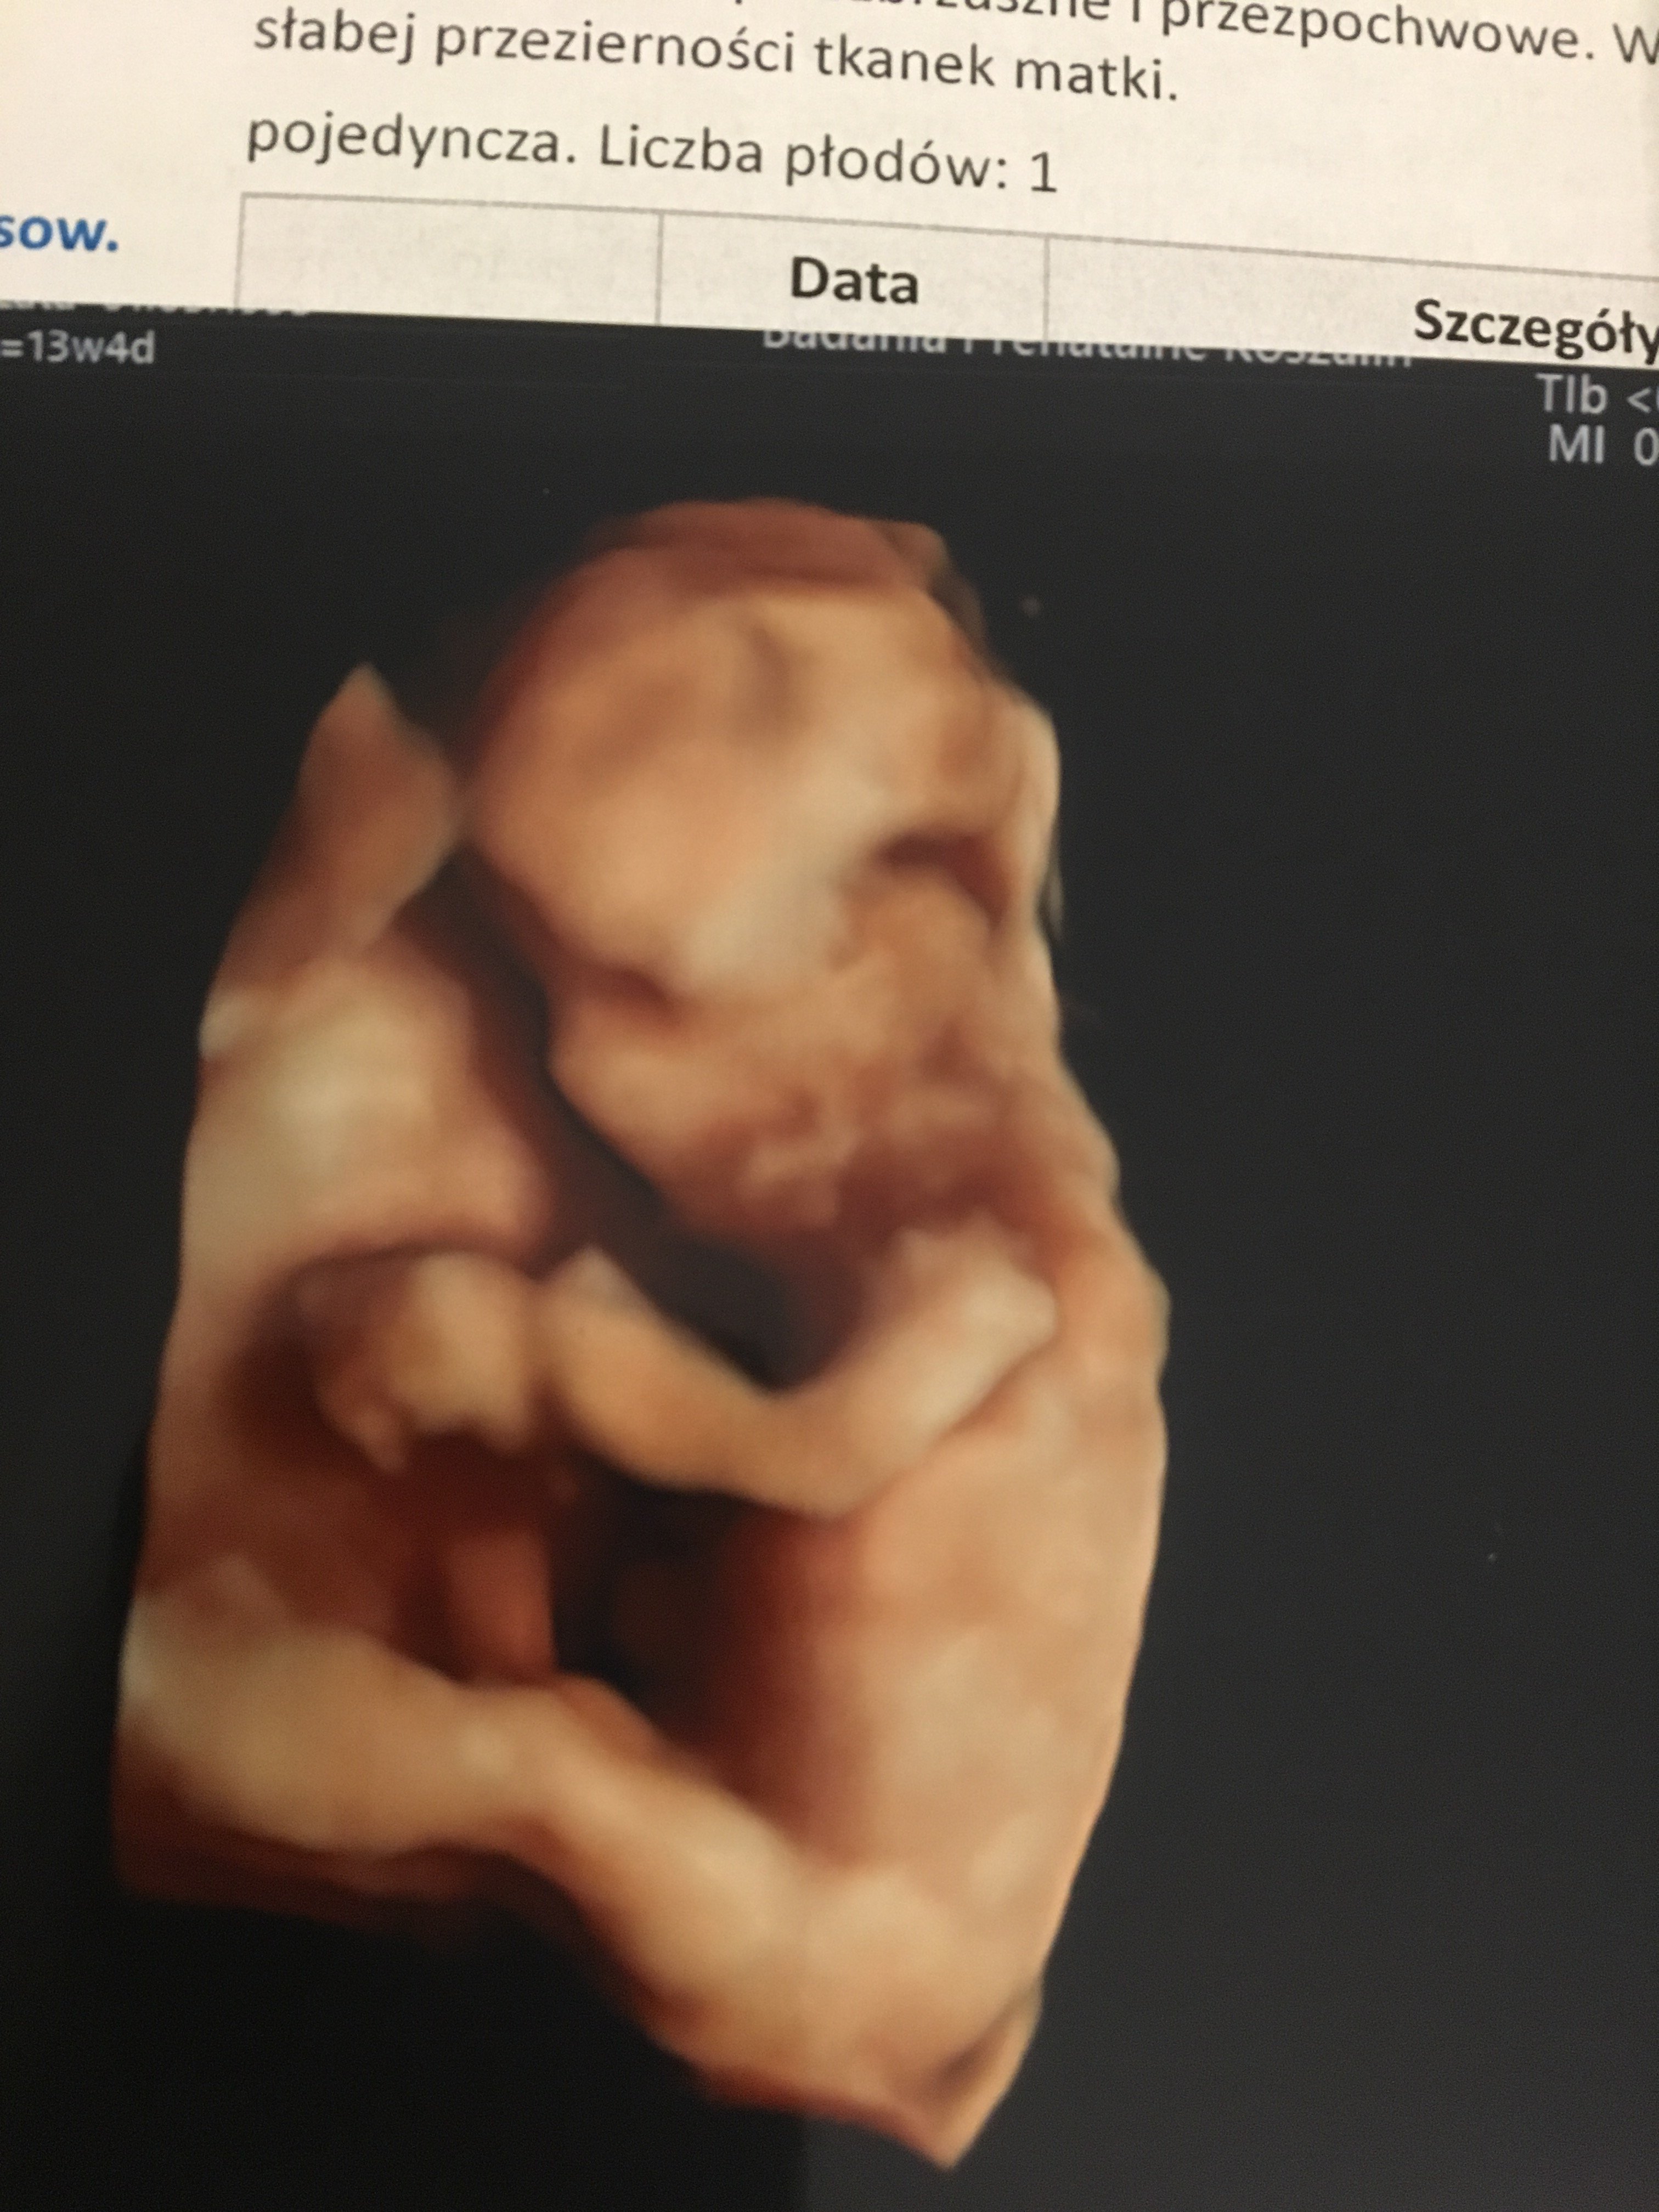

Niunia nie chciała pozować jedyne zdjęcie które udało się wyskrobać ❤️❤️❤️

Załączniki

• 610BE82A-B459-40B3-836D-4E1DE275404E.jpeg

610BE82A-B459-40B3-836D-4E1DE275404E.jpeg

1,4 MB · Wyświetleń: 134